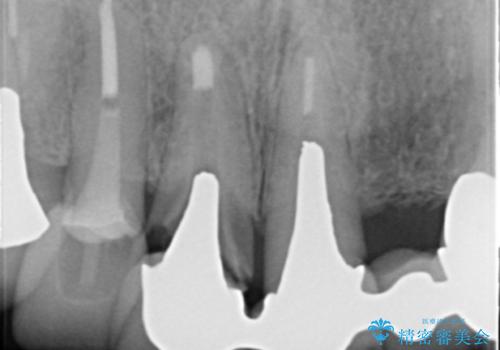

- 若い時に作った前歯のブリッジがの根元が黒くなってきているとのことで来院。

支える歯が1本虫歯がひどく、割れていました。

根の治療からやり直して新しいブリッジにしています。

ブリッジの支台歯は、根の再治療を含めて行なっています。